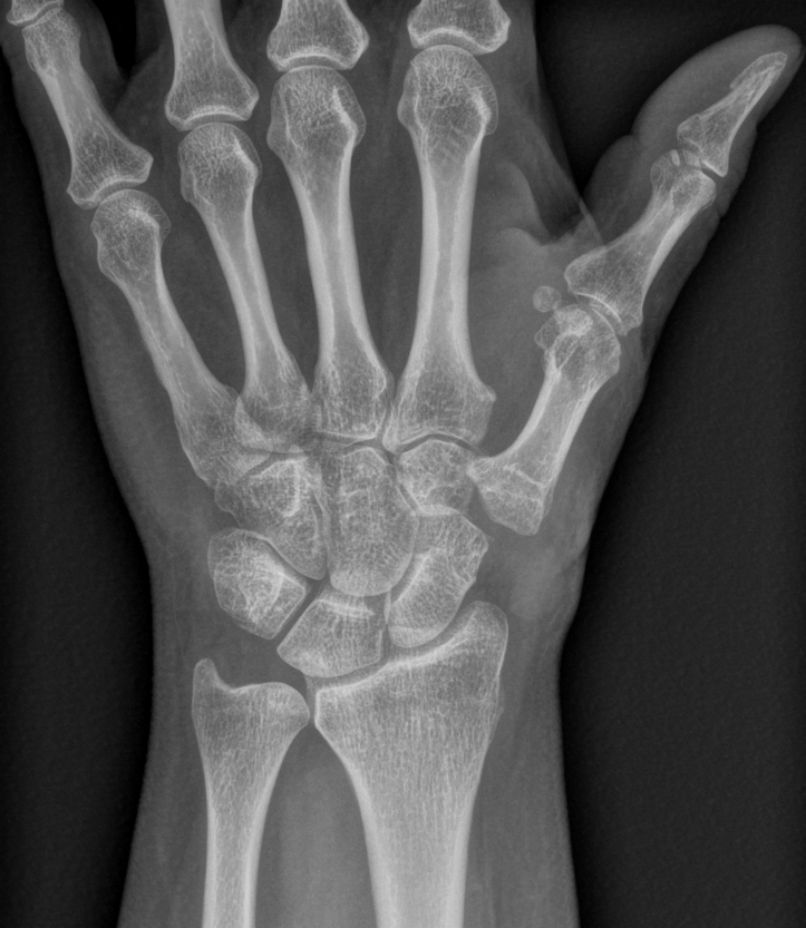

Les radiographies de face et de profil du pouce,et les incidences de Kapandji permettent de confirmer le diagnostic clinique et d’apprécier l’importance de la destruction articulaire et la conservation d’un certain volume osseux. On recherche également avec ces radiographies une atteinte arthrosique des autres articulations de la main qui peut être associée.

La rhizarthose c’est l’arthrose de la base du pouce. Elle atteint l’articulation entre le trapèze et le premier métacarpien.

Peu à peu, l’articulation se détériore puis se sub-luxe et apparaît alors une déformation caractéristique à la base du pouce. Dans les forme anciennes le pouce se déforme en "Z".